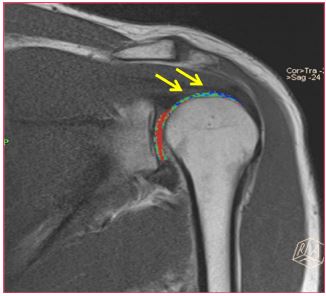

A 29-year-old man presented with a one-year history of left shoulder pain, which increased with range of motion and further aggravated on gym training. The patient underwent Magnetic Resonance Imaging (MRI) of the shoulder, which revealed significant hypertrophy of the coracohumeral and superior glenohumeral ligaments on normal grey scale images (Figure 1). We performed cartigram (T2 relaxometry) and the necessary post-processing techniques such as colour mapping (Figure 2a) and T2 values (Figure 2b) on coronal plane (where maximum glenohumeral cartilage can be seen) with a 1.5 Tesla MRI machine (SIEMENS MAGNETOM Avanto, Siemens Medical Solutions USA, Inc., PA, USA).

Figure 1: : Proton density images -coronal plane.